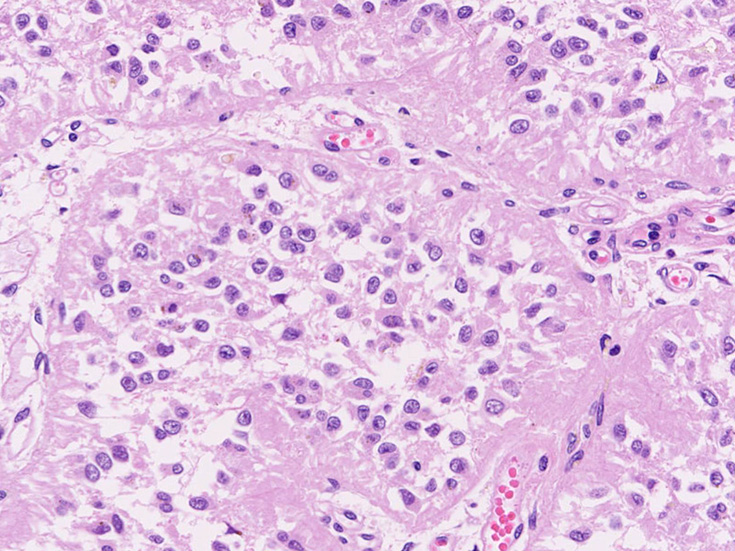

松果体の組織像

normal pineal gland tissue